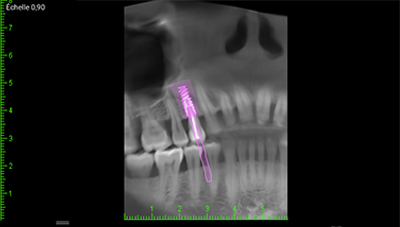

Fig. 03 : CBCT et planification implantaire (Nobel Active 3,5×13).